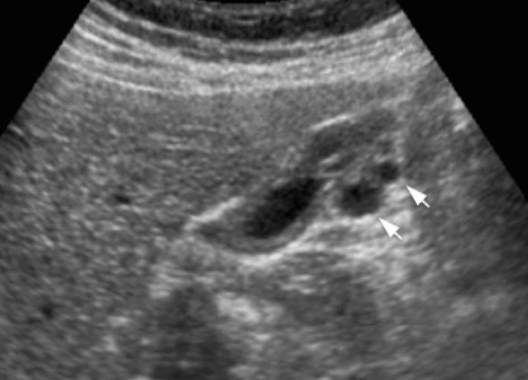

- 미세낭종의 벽에 부딪혀 다중반사를 형성 (comet-tail artifact )

- 소낭종 (anechoic)

- 소낭종내담석에 의한 comet tail sign

- GB wall 이 두꺼워진다